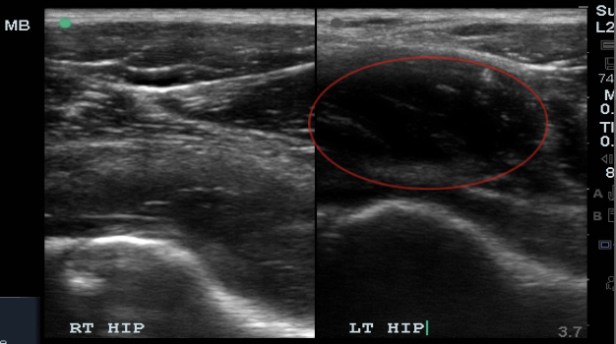

A collection that is not acute may not appear purely anechoic. However, there ought to be asymmetry when compared to the contralateral hip.

A large mass like collection was identified in this patient. It was initially assumed to be a large joint effusion, but on further evaluation it was less clear if the collection was within the joint capsule or just outside the capsule. I believed the collection was just outside the joint and likely pyomyositis. A radiologist at the bedside believed it was most likely within the hip joint.